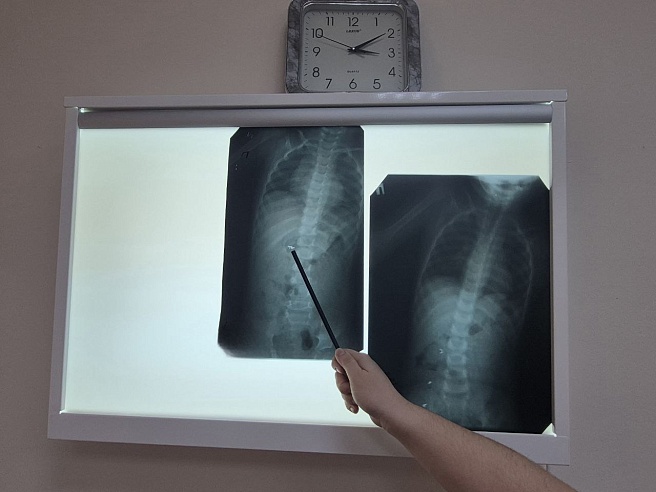

В Хвалынской больнице был сделан рентгеновский снимок - инородное тело находилось в желудке. Малыша перенаправили в Балаково. Контрольный снимок показал, что инородное тело состоит из трех частей и находятся они уже не в желудке, а распределились по кишечнику.